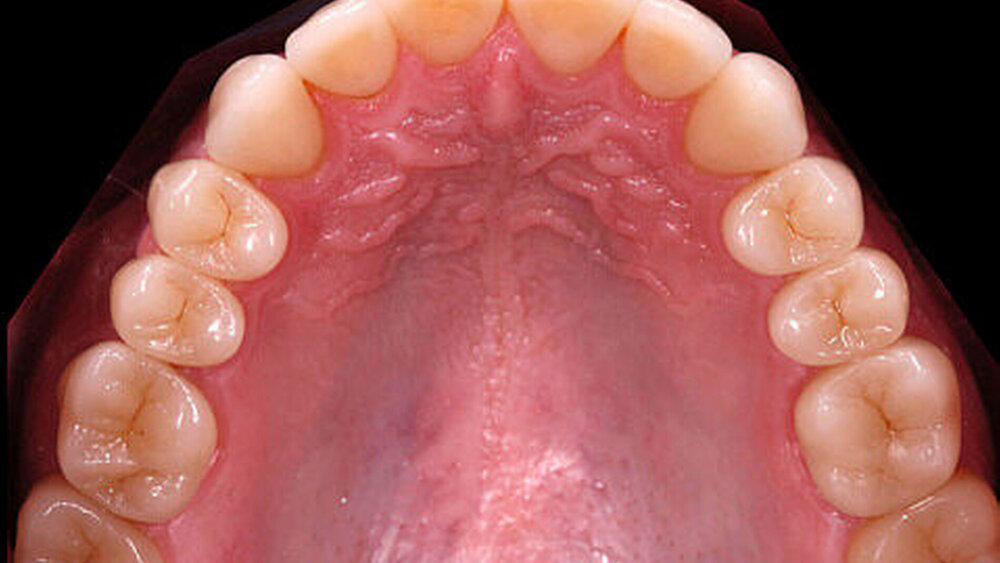

Nach einer klinischen Funktionsanalyse (Abbildungen 1 und 2) werden Situationsmodelle hergestellt und diese anhand einer arbiträren Scharnierachsbestimmung und eines Zentrikregistrats im Artikulator montiert. Die für die spätere Versorgung funktionell und ästhetisch ideale Vertikaldimension wird durch ein analytisches Wax-up eingestellt (Abbildung 3). Dieses wird in eine diagnostische Schablone (Tiefziehfolie) für eine „ästhetische Evaluierung“ durch den Zahnarzt und den Patienten überführt. Dazu kann die Schablone mit niedrigviskösem Komposit gefüllt und reversibel auf die mit flüssiger Vaseline isolierten Zähne gesetzt werden. Findet dieser Restaurationsvorschlag die Zustimmung des Patienten, wird im zahntechnischen Labor eine in der Höhe und in der Bisslage dem Wax-up entsprechende Repositionsschiene mit Front-Eckzahn-Führung angefertigt. Diese Schiene sollte circa drei Monate möglichst permanent getragen werden. Diese „funktionelle Evaluierung“ dient dazu zu prüfen, ob der Patient die neue Bisslage beschwerdefrei toleriert [Edelhoff et al., 2013; Harper, 2000; Rivera-Morales et al.,1992].